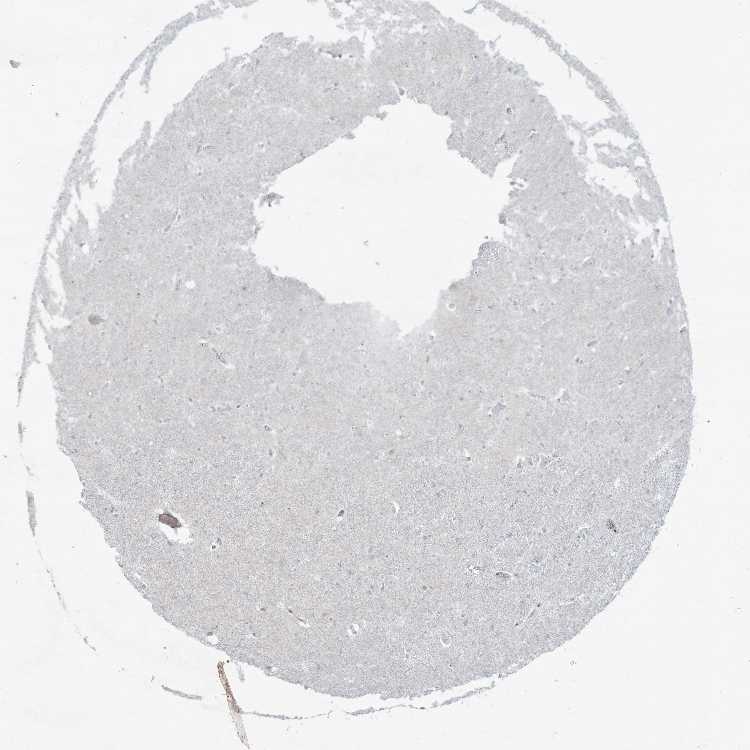

Antibody staining in the annotated cell types in the current human tissue is reported as not detected, low, medium, or high. This score is based on the staining intensity and fraction of stained cells.